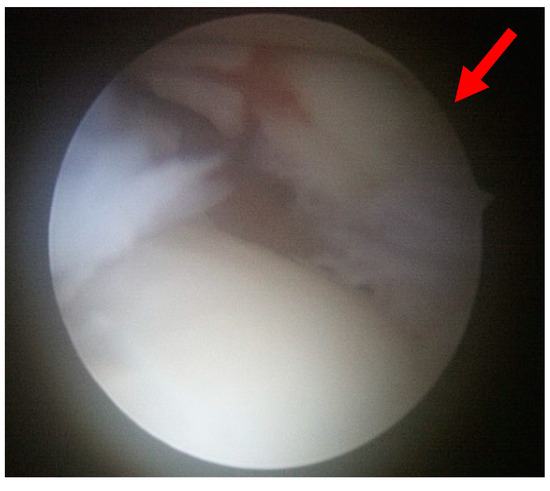

All procedures were performed by a single surgeon (W.J.K.). Patients were administered either general or spinal anesthesia or a lower extremity nerve block and were positioned supine during the surgery. The surgical area was cleaned and draped in a sterile manner, with a tourniquet inflated to ensure a clear view of the surgical field. The joint was irrigated through arthroscopy and was subsequently examined for any joint lesions or syndesmosis instability (Figure 2). Instability was defined as the tibiofibular joint space exceeding 2 mm upon probing or when the ankle was externally rotated.

Figure 2. An avulsed Wagstaffe tubercle fracture (red arrow) is observed on arthroscopy.